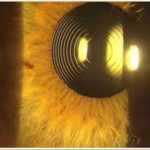

LENS BEING IMPLANTED